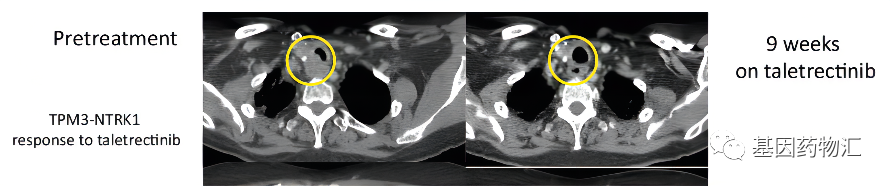

甲状腺乳头状癌:33.4个月,至发布时仍处于缓解

这位TPM3-NTRK1融合突变的转移性甲状腺乳头状癌患者,通过Taletrectinib(AB-106)治疗取得了相当不错的疗效。他用药后的缓解持续时间已经达到了33.4个月,并且至结果发布时,仍在刷新着这个数据,持续保持临床缓解!

他之前已经接受过非常多的治疗,包括甲状腺切除术、放化疗、放射性I-131治疗、索拉非尼治疗,甚至接受过了3个靶向治疗联合或不联合免疫检查点抑制剂的Ⅰ期临床试验。能够继续达到这样长的缓解期,疗效可谓相当出色。